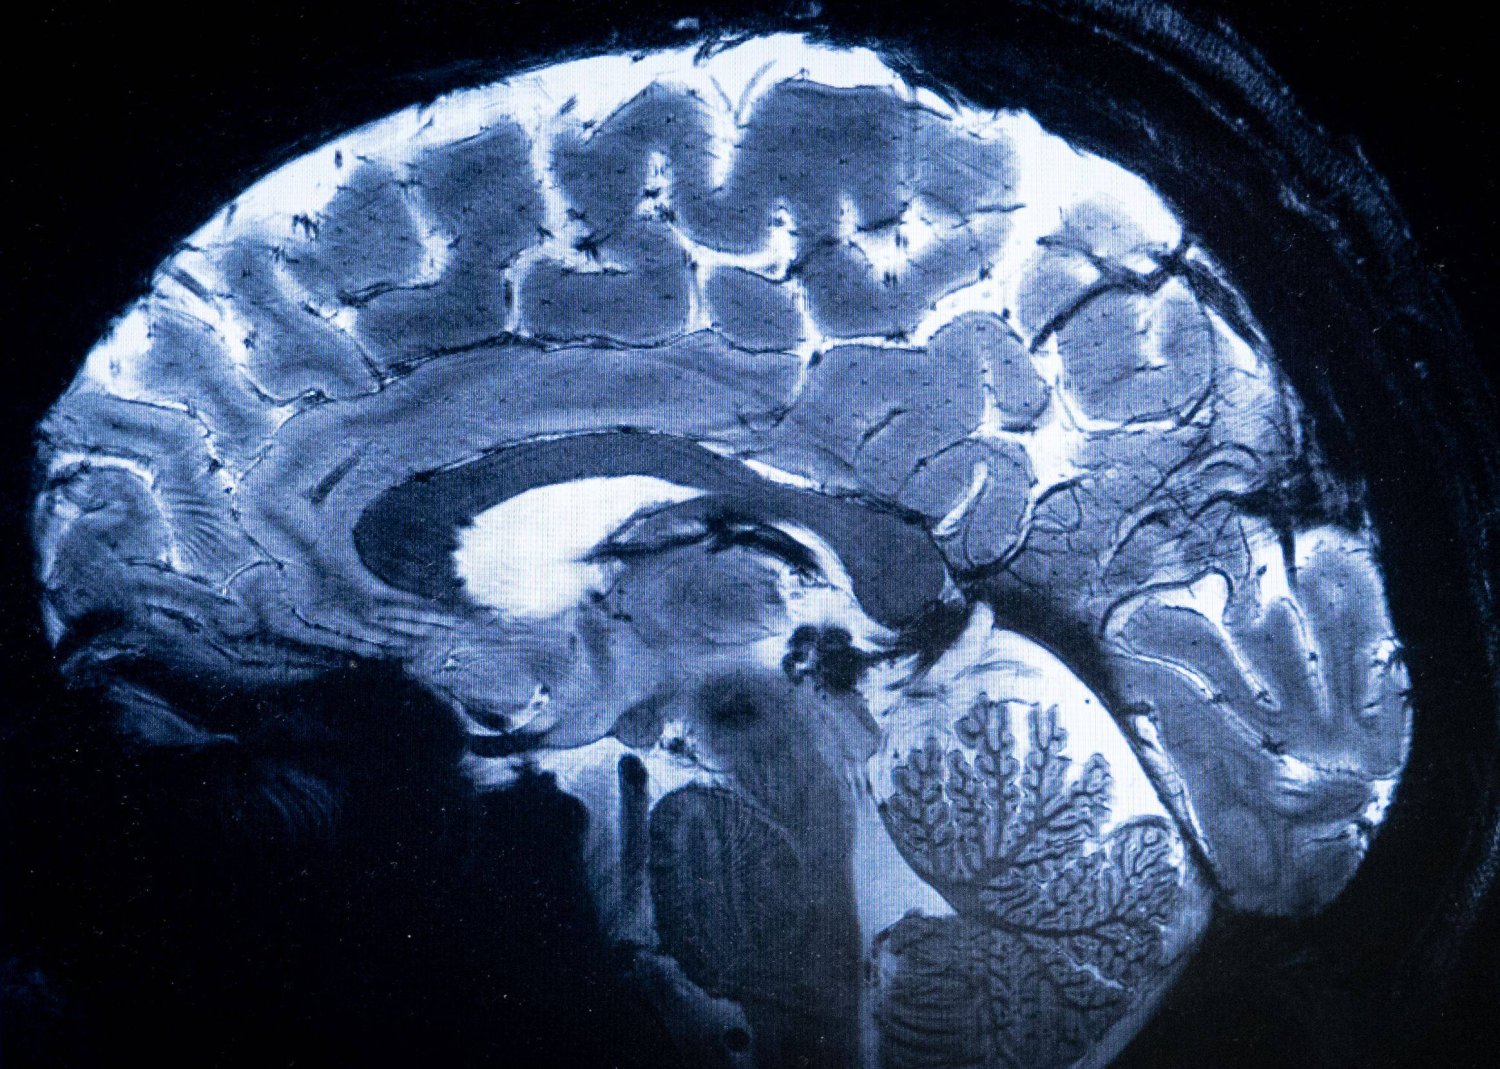

وتشير الأبحاث إلى أن ممارسة الرياضة تعمل على تحسين العمليات الإدراكية والذاكرة، مع زيادة سمك القشرة المخية، المسؤولة عن مهام مثل اللغة والتفكير والعواطف.